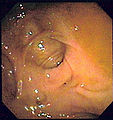

Images